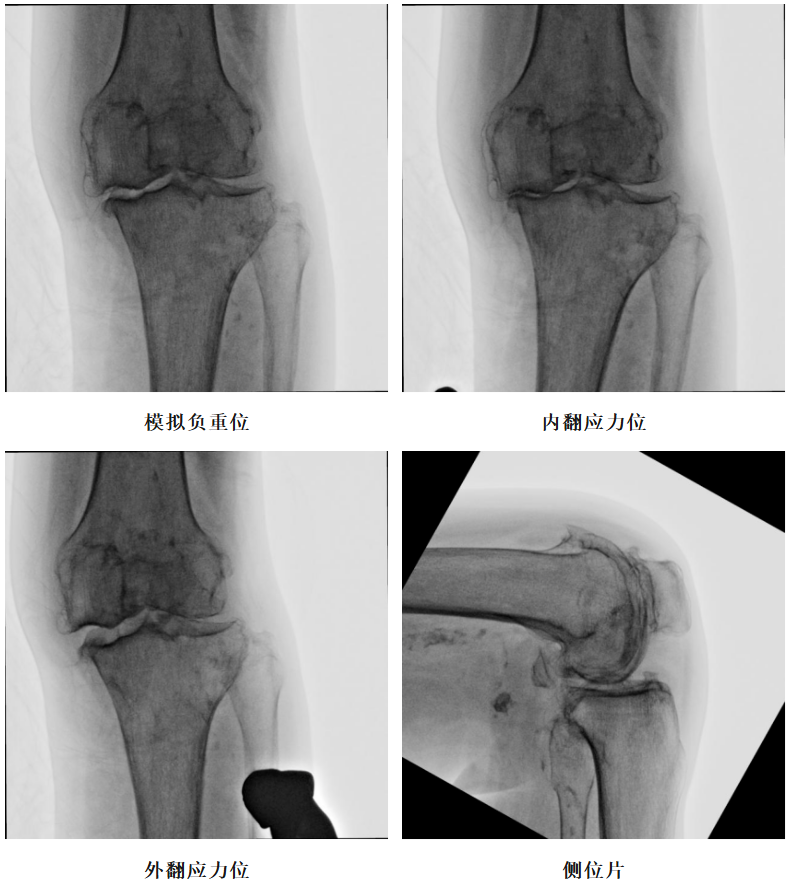

体格检查:左膝内翻畸形,约6°,无屈曲畸形。屈曲20°外翻应力下内翻畸形可纠正,屈曲90°可自行纠正。内侧关节间隙处压痛阳性。活动度:0°~110°。

X-Ray:左膝内侧间隙明显狭窄,站立位内侧间隙消失,外侧间隙正常,膝关节稳定。

术前透视片